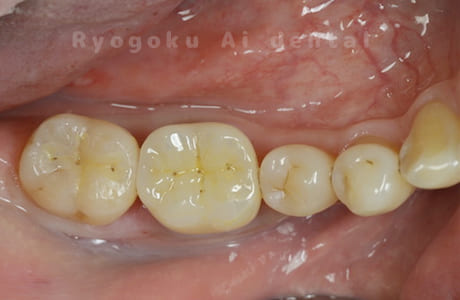

Case02

- 縁下カリエス、慢性根尖性歯周炎、不良補綴

- 治療期間

- クラウンレングスニング、マイクロエンド、フルジルコニアクラウン

- 約840,000円

虫歯が神経まで及ぶと共に、歯茎の中まで虫歯が及んでいました。根の治療(マイクロエンド・根管治療)を行なった後、クラウンレングスニング・歯周外科を行い、ジルコニアの被せ物を行った患者様です。

<リスク・副作用>

過度の咬合や衝撃で割れることがあります。